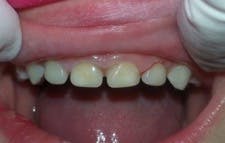

A strip crown technique (in this case, Activa BioActive-Restorative) requires fewer steps, takes less time, offers a better seal against secondary caries, and provides a more durable and fracture-resistant restoration. First, I trim and prefit Nowak strip crowns so they are even with the sulcus (figure 2). Because the prep in these cases is usually quite minimal, I typically do not need local anesthetic.

I prep the teeth with a No. 4 or No. 6 round bur, slowly removing decay with short, light touches. Incisal reduction is usually unnecessary, and I avoid it whenever possible. If needed, I use a very fine diamond to refine, shape, and open contacts. I only work two to three seconds at a time and keep a 2×2 gauze under the teeth for children who are uncomfortable with the water spray and suction. Figure 3 shows the final prep.